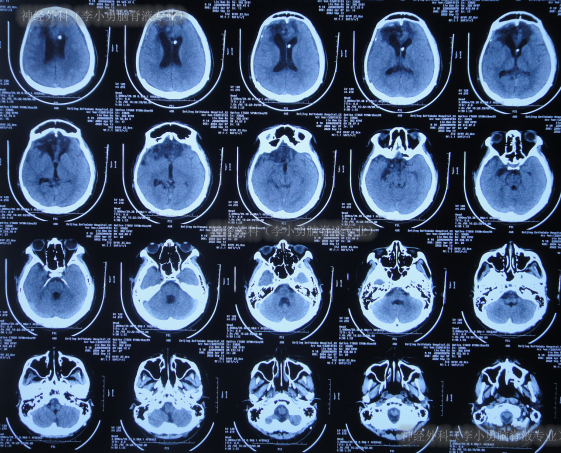

脑室腹腔分流术后31天即2022年4月28日,查头颅CT示脑室又变大(图-11)。

图-11:2022年4月28日头颅CT

虽又再次出现脑积水但2022年5月5日(脑室腹腔分流术后38天),仍进行了右侧额颞顶部颅骨缺损修补术(图-12)。

图-12:2022年5月6日头颅CT

但颅骨修补术后1周即2022年5月13日(脑室腹腔分流术后45天),患者反而出现意识变差,由清醒变为嗜睡,肢体活动也变差,且肢体肌张力增高,查头颅CT(图-13)后给予保守治疗。

图-13:2022年5月13日头颅CT

该院继续治疗半月,但患者病情进一步加重为昏迷,期间3次查头颅影像(图-14)。

图-14:3次查头颅影像

因昏迷加重于2022年6月2日(颅骨修补术后27天即脑室腹腔分流术后65天),查头颅CT示仍脑积水(图-15);进行了腰椎穿刺示颅压较高。

图-15:2022年6月2日头颅CT

因昏迷不断加重,于是家属找到北京北亚骨科医院的神经外科(李小勇脑脊液专业)。